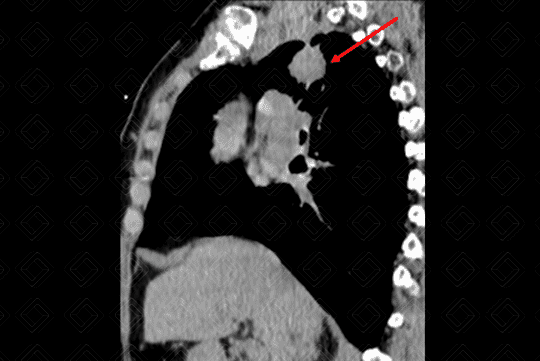

Texto alternativo para a imagem Figura 4. Créditos: Dra. Elazir Mota - Rio de Janeiro/RJ

Descrição das figuras 1, 2, 3 e 4: Tomografia computadorizada do tórax, seguida de reconstruções axiais e sagitais. Massa pulmonar, com contornos espiculados, localizada no segmento apical do lobo superior direito, medindo 3,2 cm x 1,5 cm x 2,2 cm (setas vermelhas).

Lembrando que, acima de 3 cm, a lesão já deve ser descrita como massa. Lesões menores que 3 cm são descritas como nódulos. Isso também é importante no estadiamento TNM (lesões ≥ 3 cm já são consideradas pelo estadiamento como T2).